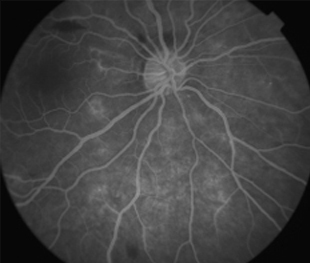

Angiografía OI